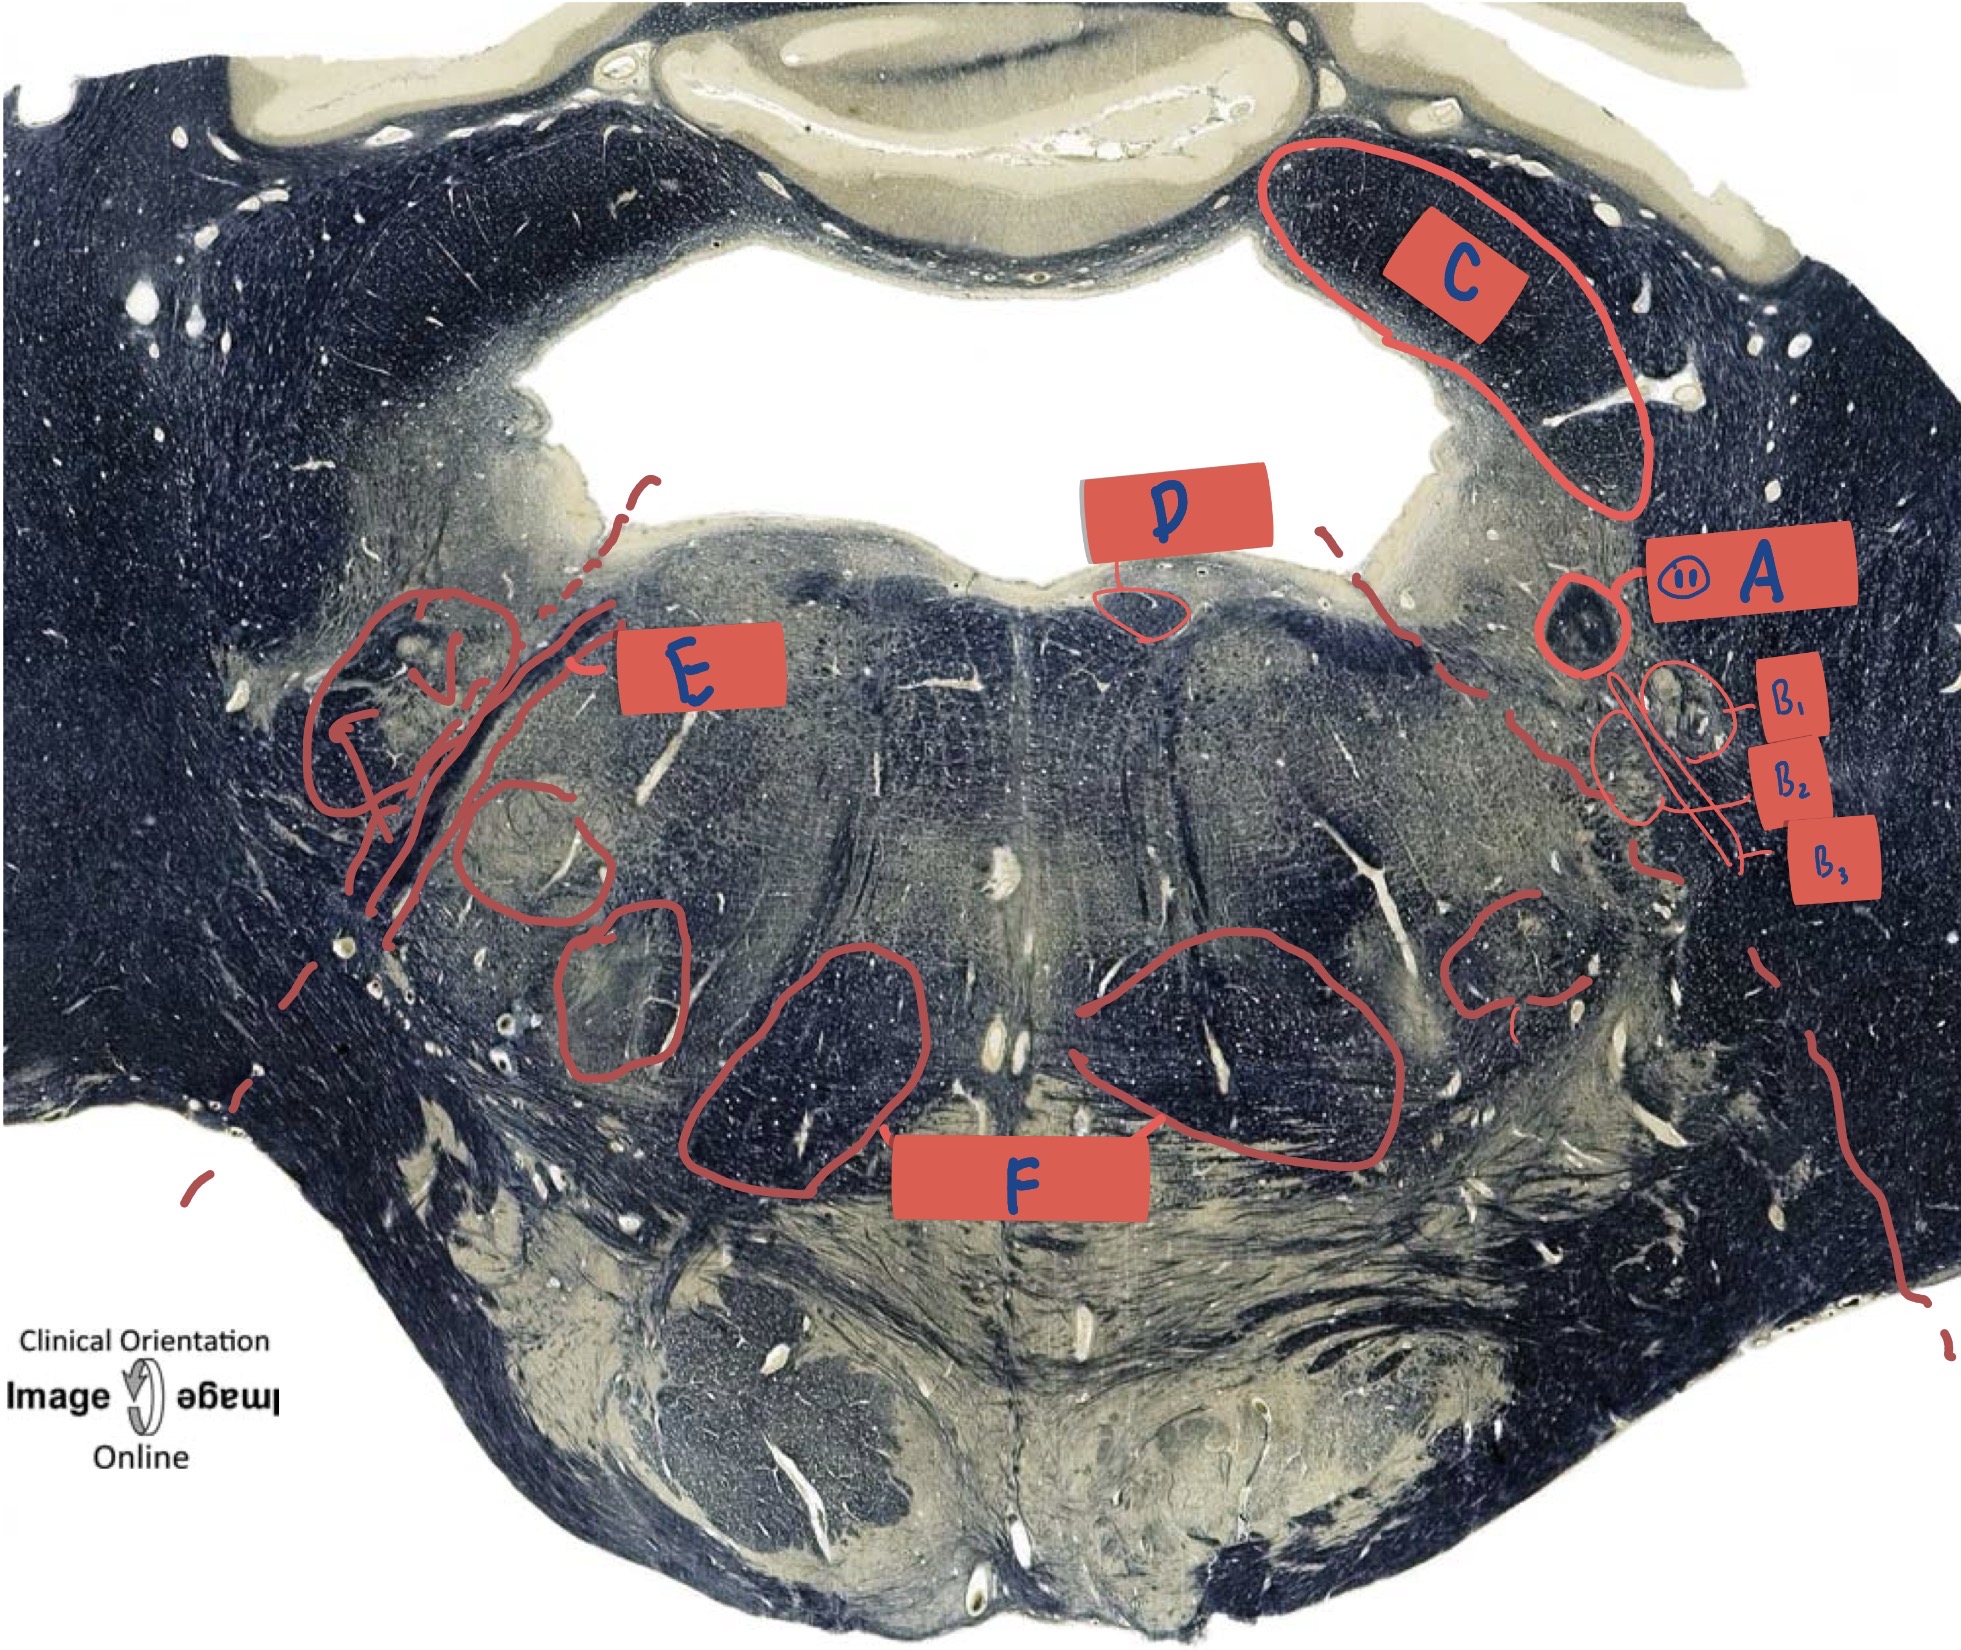

What is A?

Hypoglossal nucleus

What is B

Dorsal motor nerve of Vagus

What is C?

Solitary Nucleus

What is D?

Nucleus ambiguus

What is E?

Medial lemniscus